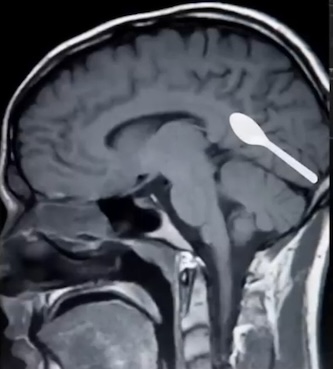

Not that long ago research was done on the brains of deceased humans to look for plastic content. The research, conducted by Professor Matthew Campen, University of New Mexico, revealed that the plastic content of their brains was found to be 0.5% on average for each individual. -That’s the equivalent of a plastic spoon weighing 5g. Hence the above image showing a plastic spoon pasted on the brain.

The 0.5% result was a 50% increase on comparing average brain plastic content in 2016.